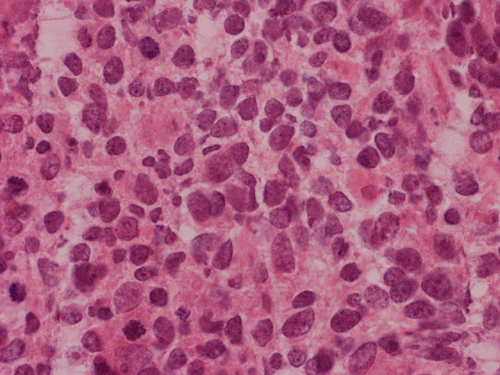

The volume of tissue received for examination amount to an aggregate of 4.0 x 2.0 x 1.5 cm in combined size. Grossly, the tissue is soft and has a creamy color with hemorrhage. The intraoperative cytologic preparation demonstrate a neoplasm composed with small to medium sized blue cells that smear out rather homgeneously and evenly. If you pay attention, there are some larger cells with a substantial amount of cytoplasm even at low magnification (Panel A). On high magnification, the nuclei are rather uniformly large, with high grade of pleomorphism, and almost all cells contain a distinct nucleoli. Apoptotic bodies and mitoses are frequent (Panel B). There are also large cells with prominent nucleoli and substantial amount of eosinophilic cytoplasm. These cells are suggestive of rhabdoid cells but none of them have the distinct inclusion body like cytoplasmic eosinophilic body of the rhabodid cells in atypical teratoid rhabodid tumor (Panel C). In the frozen section, both small to medium sized cells and cells with large nuclei with large, prominent, and eosinophilic nucleoli (Panel D and E). In the permanent sections, there is extensive necrosis (Panel F). The histology is in general agreement with that of frozen section except that the tumor cells appear to have more cytoplasm and more plemorphic, large nuclei with prominent nucleoli in comparison to the frozen section (Panel G). Large cells with substantial volume of cytoplasm, large, bizarre nucleoli and prominent, eosinophilic nucleoli are also noted (Panel H). There is a generalized degree of high grade pleomorphism. Results of immunohistochemistry are as follow:

Large cell and anaplastic medulloblastomas are recognized as different variants in the new WHO classficiation 1. They share many basic features with medulloblastoma 2, 3. The most notable differences are large cell size, increased variation of nuclear size, prominent and even eosinophilic nucleoli, increased mitotic figures and number of pyknotic or apoptotic cells, and extensive, geographic areas of necrosis. In the experience of the authors, most of the tumor cells in large cell and anaplastic medulloblastomas have high nuclear to cytoplasmic ratio in a manner similar to that of the classic variant. As per the new WHO classification, large cell medulloblastomas are composed mainly of large cells with more cytoplasm than the classic variant or the anaplastic variant. In the experience of the authors, this distinction is not always possible. The case being illustrated here includes some large cells with substantial amount of cytoplasm and but these cells only represent a portion of the tumor cell population. In general, anaplastic and large cell medulloblastomas have less favorable prognosis than the classic variant of medulloblastoma. However anaplastic changes are uncommon and does not affect the prognosis in adult cases as per one study 4.